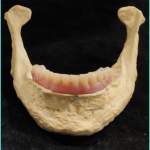

Removable Prosthesis – necessitate fewer implants. The rehabilitation, follow up and oral hygiene are easier. The procedure is cheaper. It can also easily compensate for an aesthetic defect, especially in the anterior part of the mandible14

REMOVABLE IMPLANT SUPPORTED PROSTHESIS

However, hyposalivation might lead to mucosal irritations and the significant decrease of blood vessels in the oral mucosa renders soft tissues more susceptible to traumas.

The main problem with prosthesis remains the unfavourable implant–crown ratio and axis of the implants, which is not always the same as the axis of the prosthesis, leading to torque forces that may endanger implant survival.

The use of image-guided surgery and surgical guides decreases the risk and minimises the angulation between prosthetic axis and implant axis and also allows precise planning and accuracy of the rehabilitation15,16.

DENTAL PROSTHETIC REHABILITATION OF A CLASS III DEFECT WITH ORAL IMPLANTS IN THE FIBULA AND SUPRACONSTRUCTION USING A BAR-SUPPORTED DENTURE

can also be proposed for patients wearing a removable denture, as well as O-ring retained dentures or telescopic retention17.